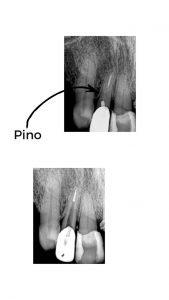

Remoçao de Pinos intrarradiculares em dentes tratados de canal

Vários são os casos em que dentes tratados endodonticamente necessitam de restauração com pinos intra-radiculares. E por necessidade de retratamento é necessário a sua remoção.

Os pinos intra-radiculares podem ser metálicos ou de fibra de vidro, fibra carbono (hoje menos utilizado), porcelana, zircônia, e outros. Os mais utilizados são os metálicos e os de fibra de vidro. Existem vários recursos utilizados para a remoção dos retentores intra-radiculares: ultrassom, brocas e saca pinos.

Os meios mais seguros são através de sistema ultrassônico, por não exigirem força mecânica contra as paredes da raiz do dente, evitando o efeito de alavanca, e por conseguinte evitando fraturas. Para tornar ainda mais eficaz, utilizamos o microscópio, que garante uma melhor visualização.

O sistema de ultrassom transforma a energia elétrica em energia mecânica. Quando age em sentidos opostos é criada uma zona de justaposição onde a soma das ondas mecânicas potencializa a ação ultrassônica quebrando o cimento com mais facilidade. Portanto deslocando o pino da sua posição original.